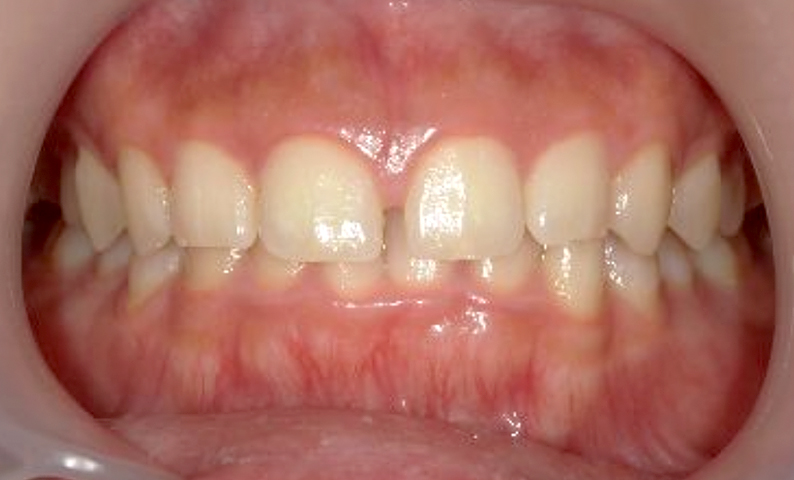

| 治療前 | 治療後 |

|---|---|

|